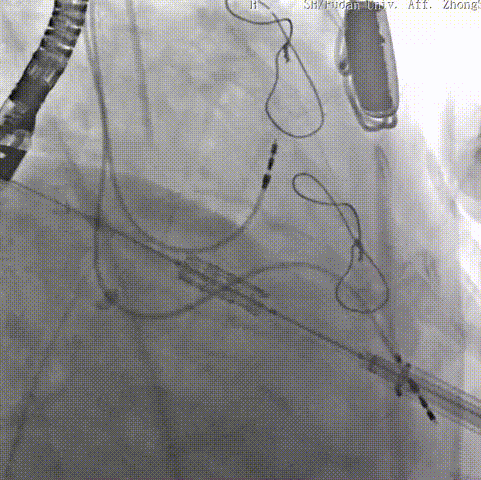

二尖瓣病例:

患者女性,73岁,既往二尖瓣位植入27# Epic猪瓣,超声提示二尖瓣人工瓣膜衰败伴重度关闭不全,瓣叶连枷。该患者还合并重度贫血、低白细胞、低血小板、多囊肝、多囊肾、永久起搏器植入术后、心功能NYHA III级、营养状况极差,术前STS评分12.1%,属于常规外科手术极高风险患者。术前经详尽影像学评估及病例讨论,考虑到患者既往经房间隔切开植入二尖瓣人工瓣膜,房间隔疤痕钙化严重增加穿刺手术风险,决定采用更安全的经心尖途径植入27号Renato球扩式瓣中瓣。

手术耗时约1小时,全程生命体征平稳,几乎无出血。瓣中瓣植入位置理想,功能表现出色:左房压自术前50/15/27mmHg降至21/11/15mmHg,二尖瓣平均流速自2.2m/s降至1.4m/s,二尖瓣平均跨瓣压差自6mmHg降至3mmHg。

▲球扩二尖瓣 ▲左室造影